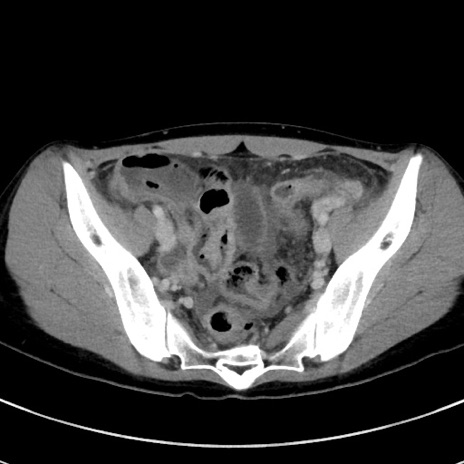

症例17(横断像)

【症例】20歳代女性

【主訴】嘔吐、下腹部痛

【現病歴】昨日夕食後に嘔吐し下腹部痛が出現。本日になっても嘔吐持続し改善しないため来院。

【身体所見】意識清明、BT 37.2℃、BP 108/67mmHg、腹部:平坦、やや硬、下腹部正中から右にかけて圧痛あり、反跳痛軽度あり、tapping pain(+)。

【データ】WBC 13600、CRP 14.94